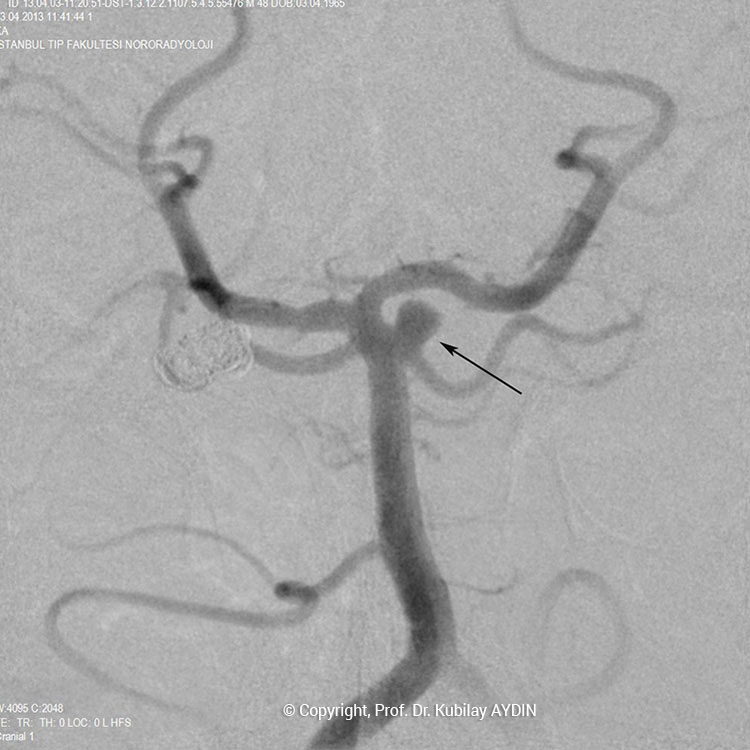

Anevrizma kesesinin damarla birliştiği noktasına, “anevrizmanın boynu” denir. Boynu geniş olan anevrizmaların tedavisinde, anevrizma içine konulacak koillerin, anadamar içine sarkmaması için yardımcı cihazlar kullanmak gerekebilir. Geniş boyunlu anevrizmaların koillenmesi sırasında özel yapıda balonlar veya stentler (metal kafes) kullanmak gerekebilir.

Geniş boyunlu anevrizmaların stent kullanılarak koillerle kapatılması işlemine “stent-yardımlı koilleme” adını veriyoruz. Bu işlemin ilk aşamasında anevrizmanın boynunu örtecek şekilde damar içine bir metal kafes (stent) yerleştirilerek, bir sonraki aşamada anevrizma kesesi içine konulan koillerin damar içine sarkması önlenir. Yani, burada stentin görevi, anevrizma içine doldurduğumuz koil adı verilen tellerin, damar içine sarkmasını önlemektir. Stent-yardımlı koilleme, geniş boyunlu anevrizmaların kapalı yöntemle tedavisinde tercih edilen bir yöntemdir.

Stent yardımlı koilleme tekniği ile anevrizma tedavisinde, anevrizmanın yerleştiği atardamar içerisine stent açılması için bir kateter yerleştirilir. Eş zamanlı olarak, anevrizma kesesi içerisine koilleme amaçlı farklı bir kateter yerleştilir. Damar içerisine bir stent açıldıktan sonra, anevrizma içerisideki kateterden gönderilen platinden yapılmış çok yumuşak yapıda koillerle anevrizma kesesi doldurulur. Stent, anevrizma içeriside bırakılan koillerin damar içine sarkmasına engel olur. Koilleme işlemine, anevrizma koillerle tamamen doldurulana ve anevrizma içine kan girmeyene kadar devam edilir.